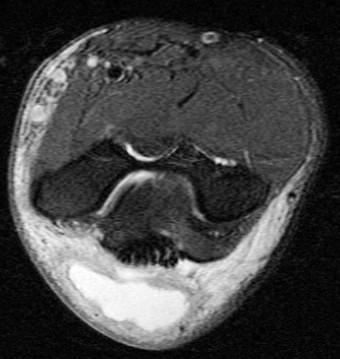

Figure 2 for case olecranon bursitis ( RID2082 )

Figure 2

Fluid and bursal lining thickening. Area edema. This was non septic. No osteomyelitis. Reference article.

olecranon bursitis ( RID2082 )